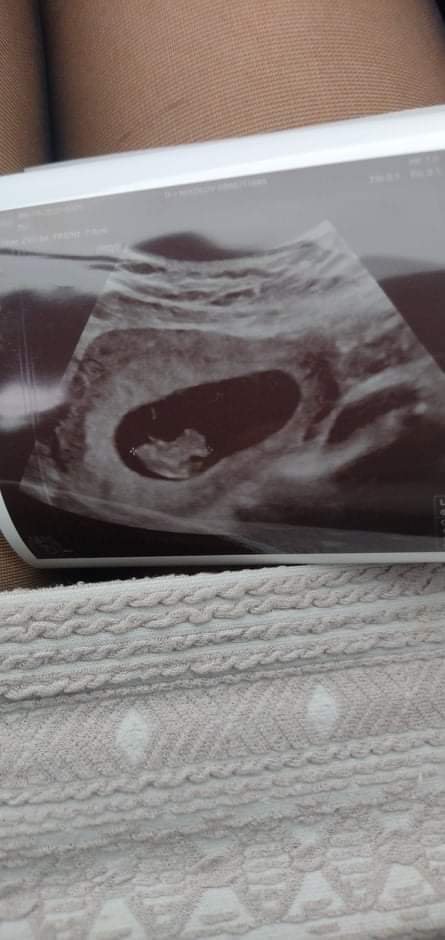

Какви са обичайните симптоми по време на бременност, особено в ранните етапи?

Симптомите на ранната бременност включват подуване и болка в гърдите, повишен апетит, умора, гадене, често уринниране, промяна в апетита и настроението. Обичайните симптоми по време на бременност могат да включват повишено кървене без мирис и цвят, коремна болка, болки в кръста, повишен глад , повишена умора и други подобни състояния. Някои жени съобщават за разлики в усещанията - от сутрешно гадене до следобяд или вечерно неразположение. Разликите зависят от индивидуалната реакция на организма към хормоналните промени.